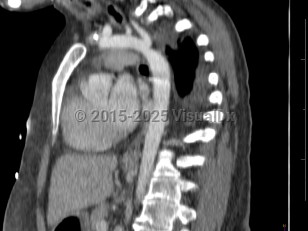

Imaging Studies image of Coarctation of the aorta - imageId=7903687. Click to open in gallery.  caption: '<span>CT image demonstrates focal  narrowing of the aorta just distal to the origin of the left subclavian  artery in this patient with known aortic coarctation.</span>'

CT image demonstrates focal narrowing of the aorta just distal to the origin of the left subclavian artery in this patient with known aortic coarctation.